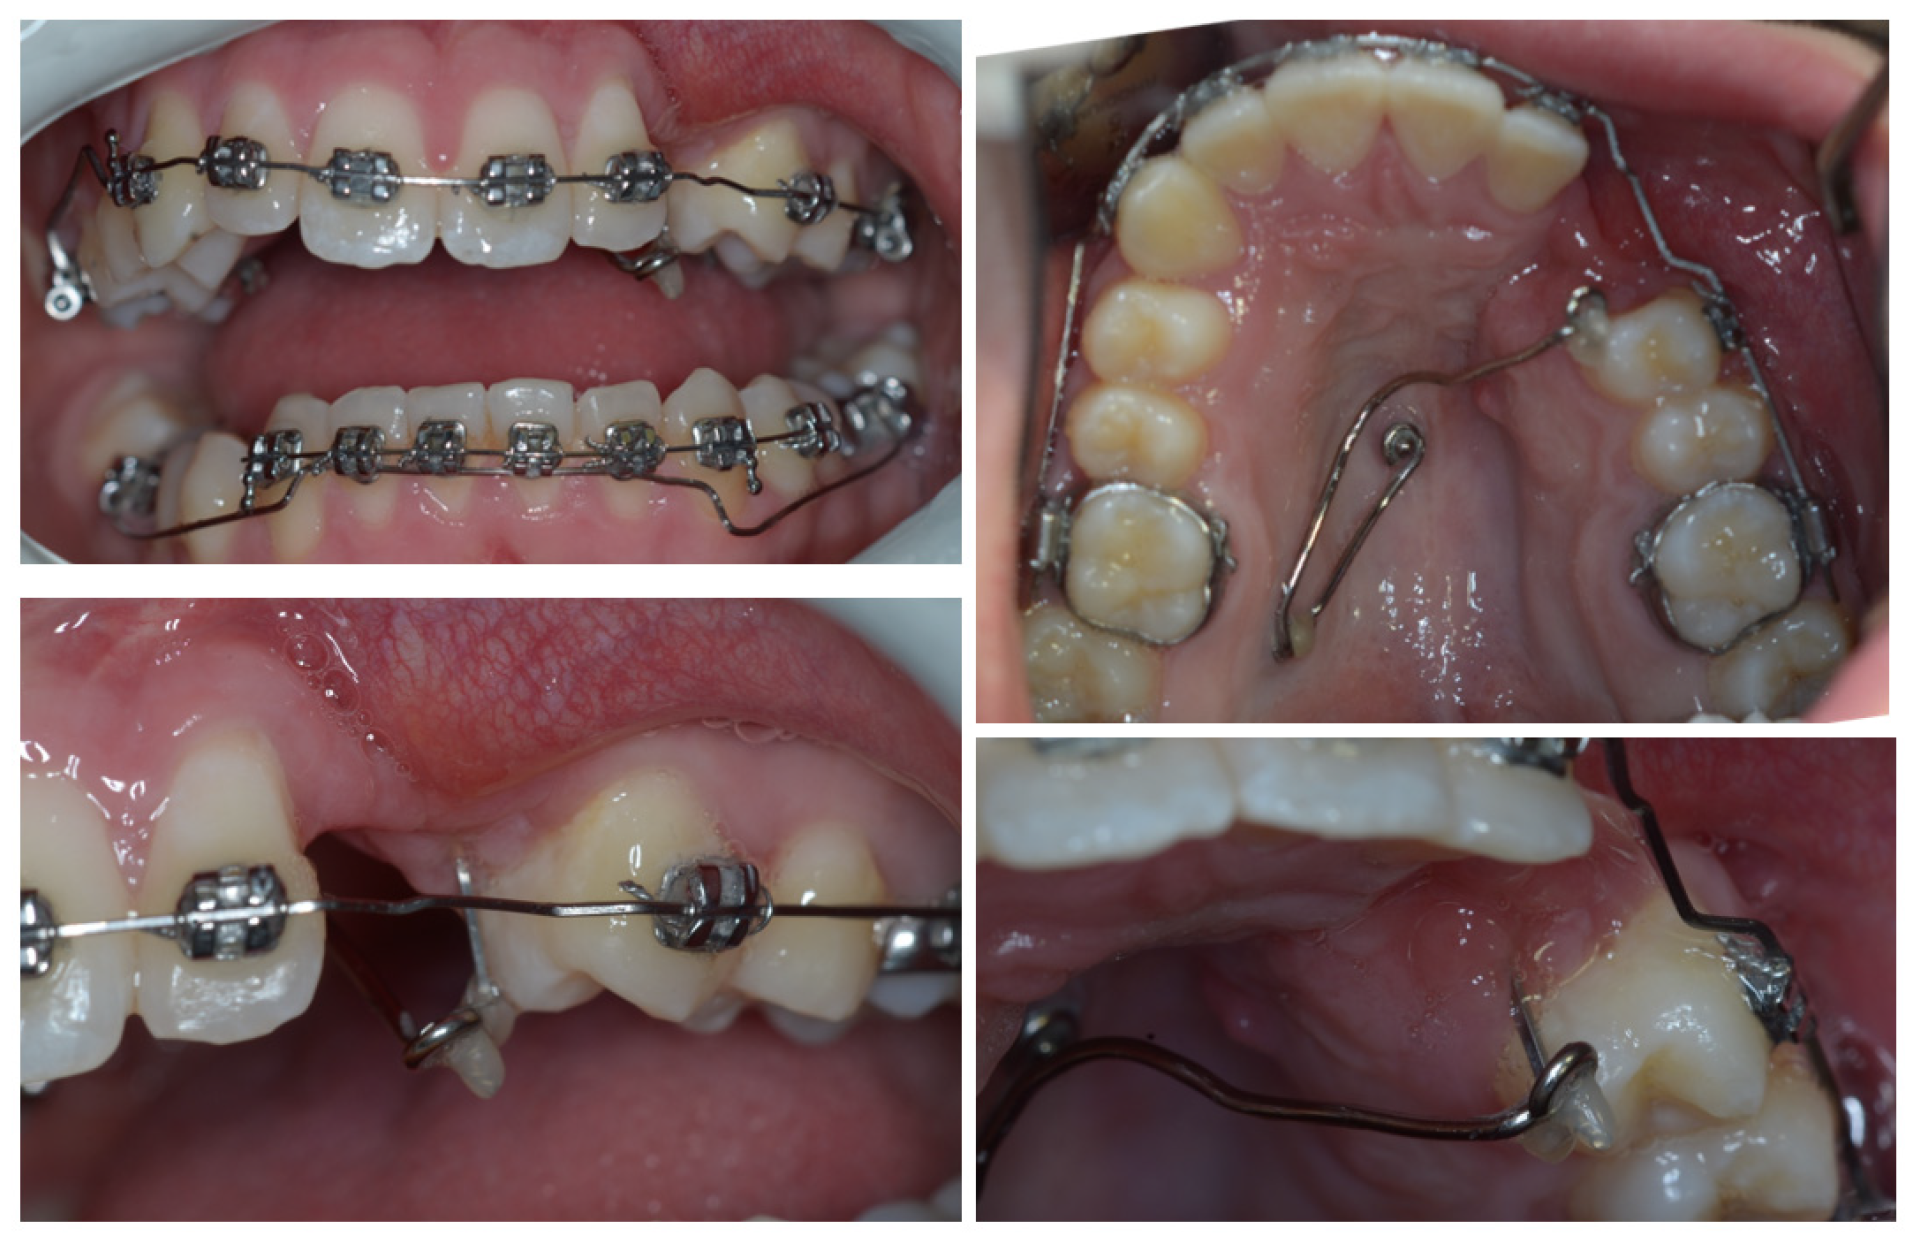

3. Therapeutic Interventions

4. Follow-Up and Outcomes